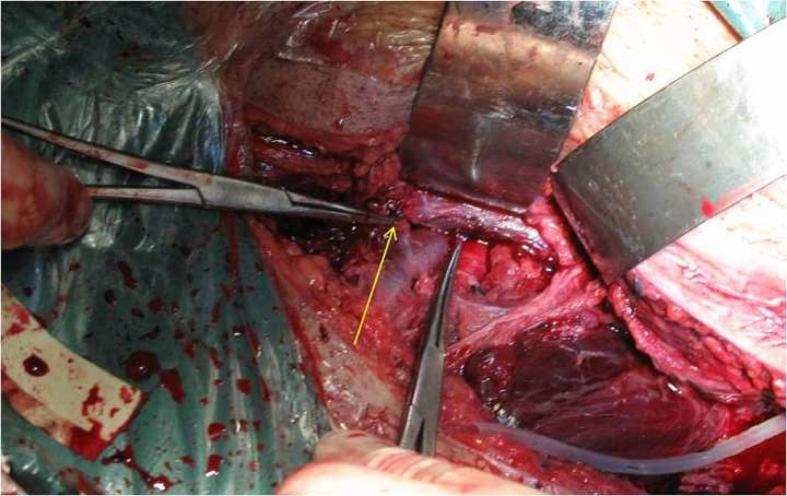

成年患者骶髂关节前脱位后隐匿性髂外静脉损伤

Occult external iliac vein injury after anterior dislocation of the sacroiliac joint in adult patient.

Anterior dislocation of the sacroiliac joint, characterized by dislocation of the ilium anterior to the sacrum, is a subtype of complete posterior pelvic ring disruption. This injury occurs mostly in children. We present an adult patient with anterior dislocation of the sacroiliac joint. It was associated with numerous complications. To the best of our knowledge, it is only the second case reported in the literature.

摘要